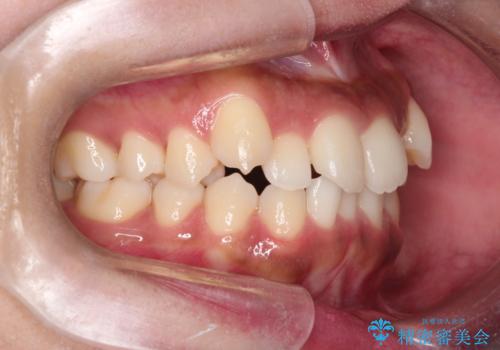

【インビザライン】笑ったときに目立つ八重歯をなおしたい

- 笑ったときに八重歯が見えることを主訴に来院されました。

下の前歯が一本足りない患者様でしたので、シミュレーションを作り、事前に患者様と治療ゴールのイメージをしっかり共有したうえでインビザラインを用いて治療を行っています。

奥歯を後ろのほうに動かすことで、前歯も少し下がることができ、矯正後の口元も満足していただきました。

下顎の前歯が一本ない場合は上下の正中は合いません。